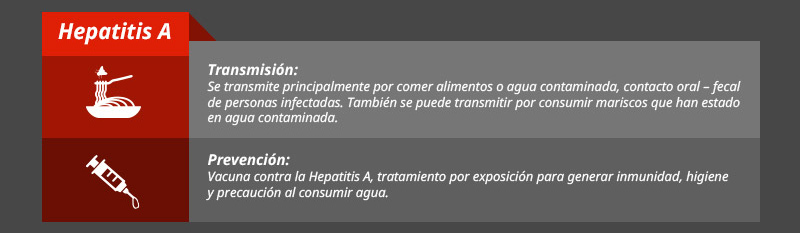

Prevención

Tipos de hepatitis